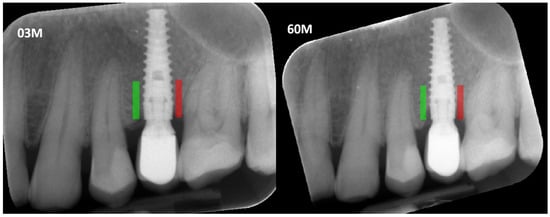

Prior to defining the regions of interest (ROIs) and measuring marginal bone loss, all radiographic images were corrected for implant long-axis alignment to standardize the analysis. ROIs were marked at consistent locations on intraoral radiographs taken at different time points: 3 months (3 M) and 60 months (60 M) during the observation period. Subsequent analyses of texture features were conducted to calculate the Corticalization Index (Figure 1).

Figure 1. Marking an ROI. ROIs were marked near the implant neck area. Green area—mesial implant neck area; red area—distal implant neck area. Abbreviations: ROI—Region of Interest; 03 M—3 months after functional loading; 60 M—60 months after functional loading.